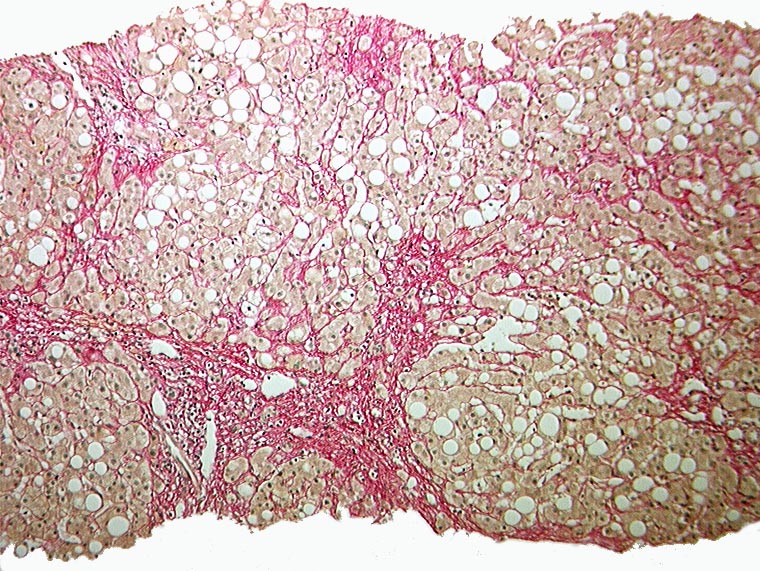

Sklerosierende Steatohepatitis, partieller zirrhotischer Umbau

Grobtropfige Verfettung. Maschendrahtfibrose. Portoportale Septenbildung.

Unvollständiger zirrhotischer Umbau mit portoportaler Septenbildung.

Aethylabusus.